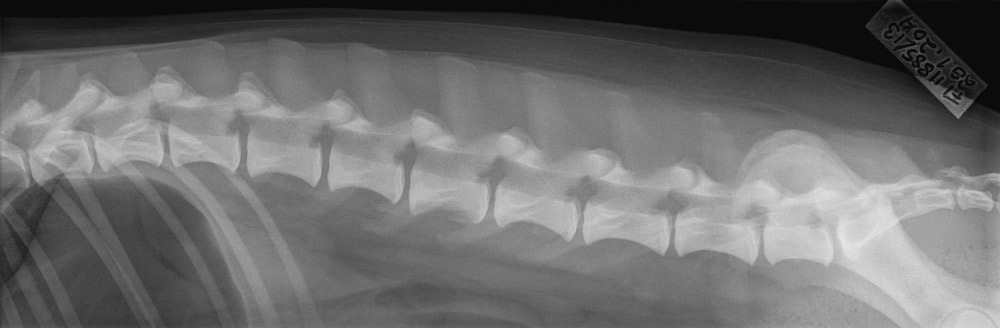

Selkälausuntomaksu tulikin sitten erillisenä, eikä siitä tullut enää sähköpostia, jonka vuoksi en huomannut sen heti olevan maksettavissa Omakoirassa. Maksun jälkeen kyseinen lausunto tuli myös näkyviin. Selästä oli lausuttu odotetusti välimuotoinen lanne-ristinikama, joka oli normaali ja sen lisäksi nikamien epämuotoisuus, josta aste 1, lievä. Lisätiedoissa näkyi kommenteissa että Tenhon viimeisestä rintanikamasta (T13) puuttui kylkiluut, eli pienet lyhyet luut jotka normaalisti ovat viimeisenä. Pienen selvityskierroksen jälkeen (lausunnon antanut eläinlääkäri) todettiin ettei puutos vaikuta koiraan mitenkään, eikä sitä näe ulospäin. Ei sitten tullut eläinlääkärin kanssa tuota huomattua, mutta ei se siis onneksi vaikuta koiraan eikä harrastamiseen. Lisäksi mainintana oli viimeisen lannenikaman olevan lyhyt ja takana ja LTV rajatapaus. Normaaliksi se oli kuitenkin lausuttu, mikä sitten lienee lyhyen ja normaalin lyhyemmän raja. Kuvista voi ihmetellä asiaa (tästä).

Aluksi hieman itsessäni ihmetystä herätti miksi tuo nikamien epämuotoisuus oli ylipäätään lausuttu, kun kennelliiton sivuilla mainitaan VA lausuttavan korkkiruuvihäntisille roduille. Tähän mennessä muilla collieilla ei näy tuloksissa sitä olevan, mutta selvisi sekin kun lueskelin kuvausohjeita, eli jos lausuttavaksi menee kuvat lanne- ja rintarangan lisäksi kuva myös kaularangasta, voidaan tuo nikamien epämuotoisuus lausua myös muille kuin korkkiruuvihäntäisille roduille.

Vähintään 3 röntgenkuvaa = rinta- ja lannerangan sivukuvat, lanne-ristiluualueen selällään otettu kuva (tai lonkkakuva, jossa alue näkyy).

Näistä kuvista lausutaan LTV.

Jos mukaan liitetään edellä mainittujen kuvien lisäksi myös kaularangan sivukuva, voidaan antaa myös VA-lausunto.